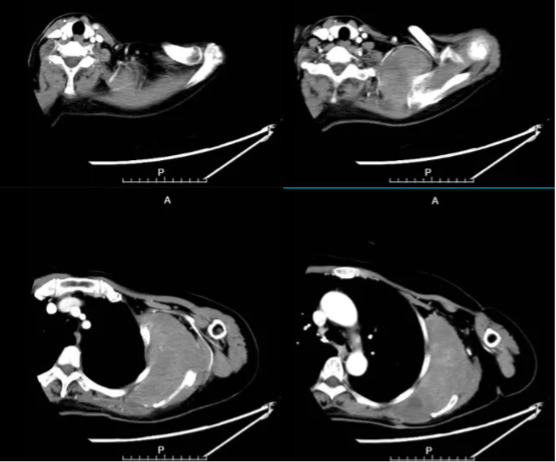

图示:上肢CTA,以左侧前锯肌为中心可见软组织肿块,约118*63*163mm。左侧锁骨下动脉及也动脉分支参与供血